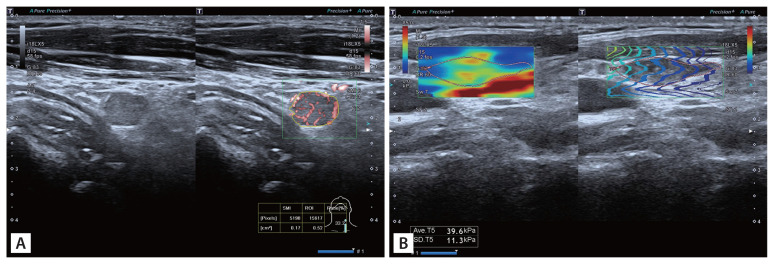

背景/目的:本研究旨在利用多模态超声参数建立一个诊断模型,以帮助检测甲状腺乳头状癌(PTC)患者的颈淋巴结转移:研究对象包括 69 名 PTC 患者的 84 个可疑淋巴结,所有患者均接受了细针穿刺,并获得了病理结果。研究分析了传统灰阶超声、剪切波弹性成像(SWE)和超微血管成像的数据。通过比较良性组和转移组的主要超声特征,利用费雪逐步判别分析建立了一个诊断模型。通过自我测试、交叉验证和接收器操作特征曲线分析评估了模型的有效性:淋巴结(X1)、皮质高回声(X2)、血管形态(X4)和 SWEmean(X7)这四个特征是判别分析中不可或缺的部分,并得出以下等式:Y1 = -3.461 + 2.423x1 + 0.321x2 + 1.620x4 + 0.109x7,Y2 = -8.053 + 0.414x1 + 2.600x2 + 2.504x4 + 0.192x7。如果 Y1 < Y2,该淋巴结将被诊断为转移性淋巴结。该模型的曲线下面积为 0.833,灵敏度为 83.33%,特异度为 83.33%:通过费雪逐步判别分析建立的多模态超声诊断模型证明能有效识别 PTC 患者的转移性淋巴结。

Methods: The study included 84 suspicious lymph nodes from 69 PTC patients, all of whom underwent fine needle aspiration with pathological results. Data from conventional grayscale ultrasound, shear wave elastography (SWE), and superb microvascular imaging were analyzed. Key ultrasound features were compared between benign and metastatic groups to create a diagnostic model using Fisher's stepwise discriminant analysis. The model's effectiveness was assessed with self-testing, cross-validation, and receiver operating characteristic curve analysis.

Results: Four features, namely lymphatic hilum (X1), cortical hyperechogenicity (X2), vascular pattern (X4), and SWEmean (X7), were integral to the discriminant analysis, resulting in the equation: Y1 = -3.461 + 2.423X1 + 0.321X2 + 1.620X4 + 0.109X7, Y2 = -8.053 + 0.414X1 + 2.600X2 + 2.504X4 + 0.192X7. If Y1 < Y2, the LN would be diagnosed as metastatic lymph nodes. The model demonstrated an area under the curve of 0.833, with a sensitivity of 83.33% and specificity of 83.33%.